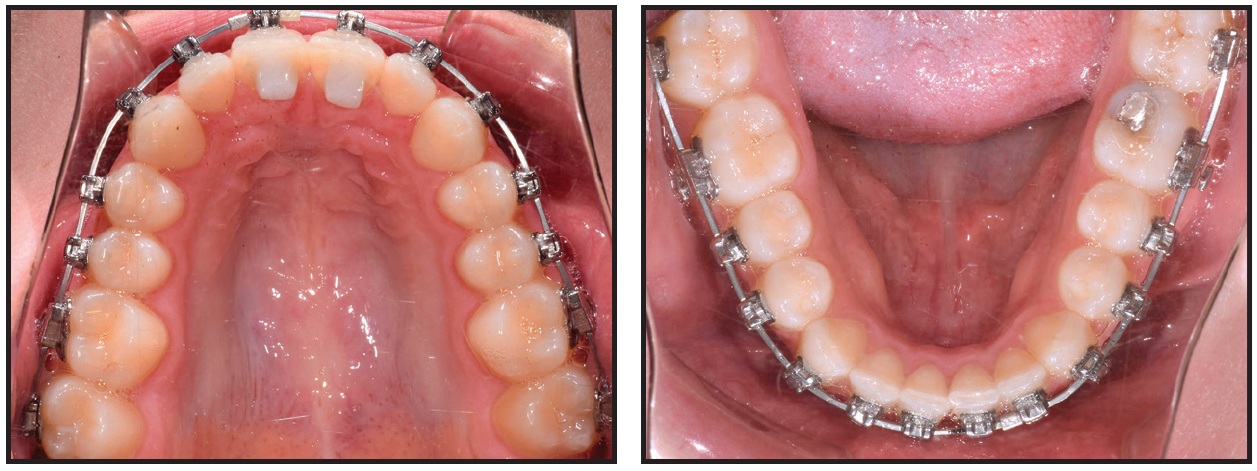

Damon Q** brackets were bonded to all teeth in both arches: low-torque brackets on the upper and lower incisors, high-torque brackets on the lower canines, and standard brackets on all other teeth (Fig. 5). Anterior bite turbos were bonded to the lingual aspects of the upper central incisors. SmartArch .016" Copper NiTi archwires were inserted in all brackets, with no elastics worn at the start.

Fig. 5 Case 1. Damon Q** brackets bonded and .016" SmartArch Copper NiTi wires placed in both arches.

After five weeks of treatment, the upper right second molar was rebonded, and maxillary and mandibular archwires were changed to .018" × .025" SmartArch Copper NiTi (Fig. 6). The turbos remained in place.

Fig. 6 Case 1. After five weeks of treatment, .018" × .025" SmartArch Copper NiTi wires placed in both arches.